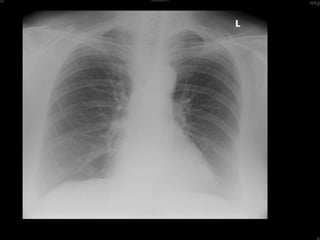

Investigation RF  458 FBC  (N) ESR  39 CRP  50 U&E  (N),  LFT  (N) X-ray hands, Feet & CXR